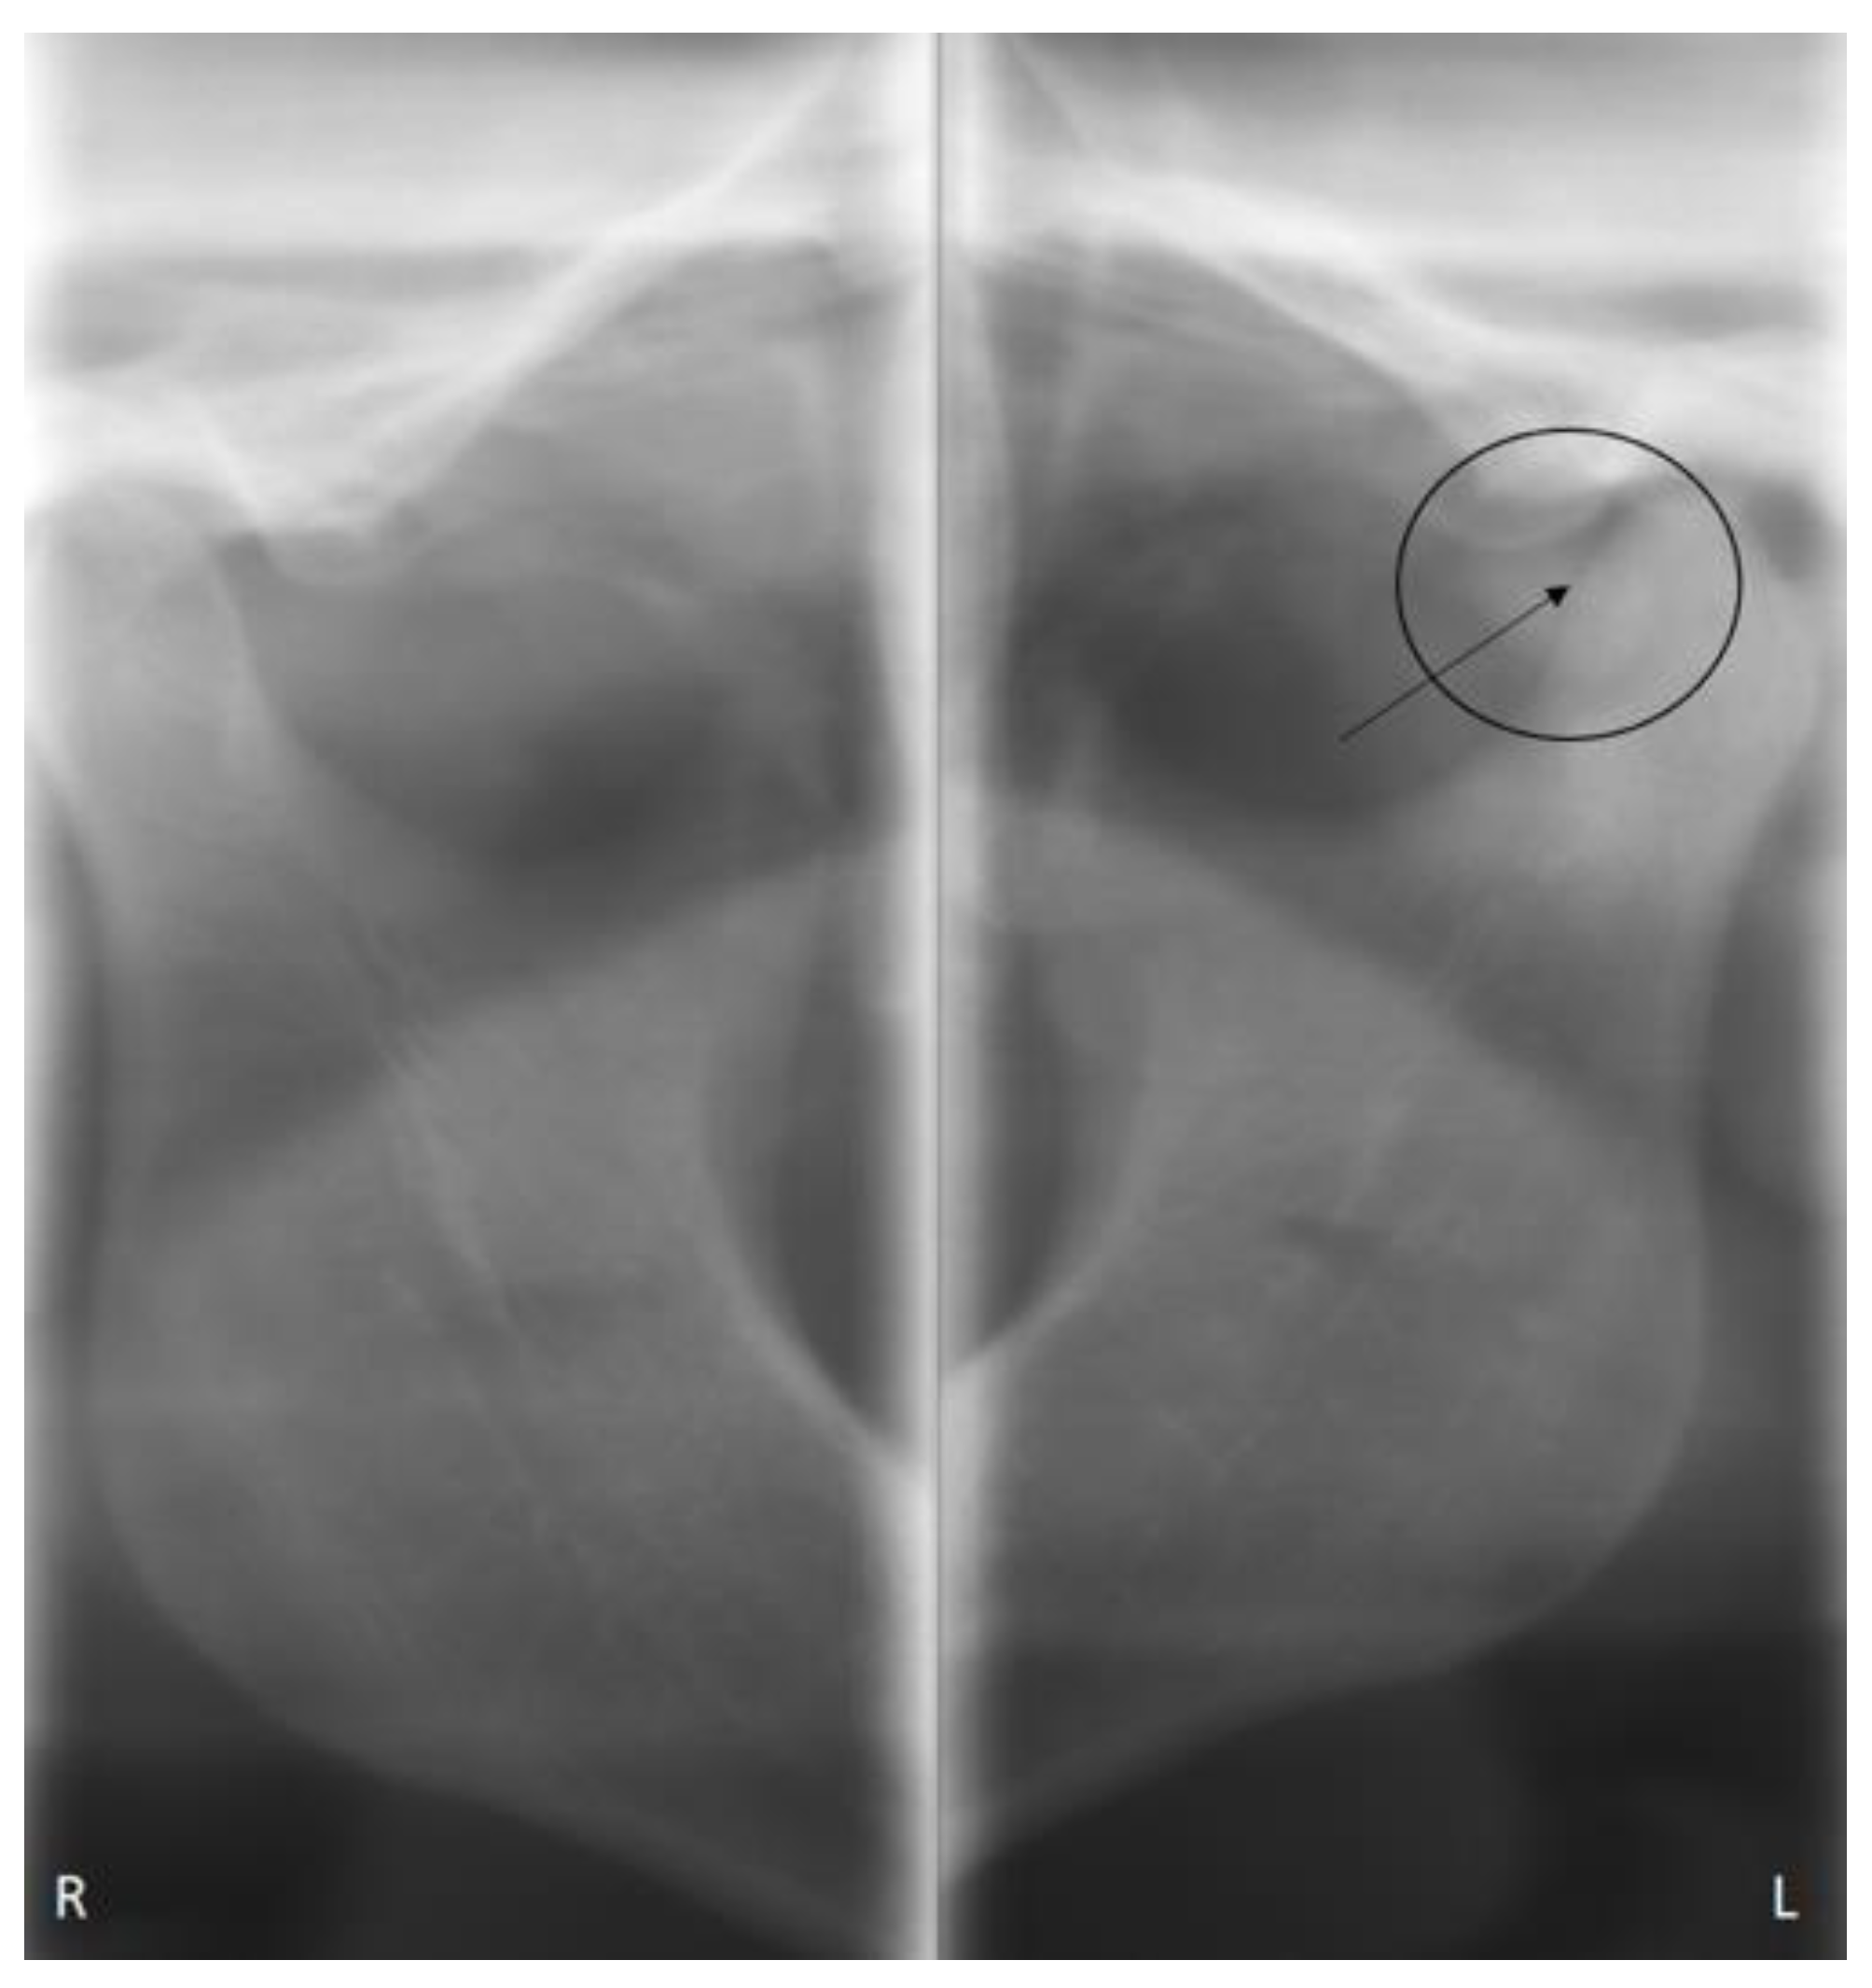

2. Case Presentation